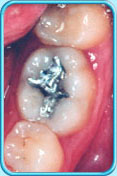

图中所见是蛀坏的牙齿补牙前的外貌。补牙前

图中所见是蛀坏的牙齿以汞合金填补后的外貌。补牙后